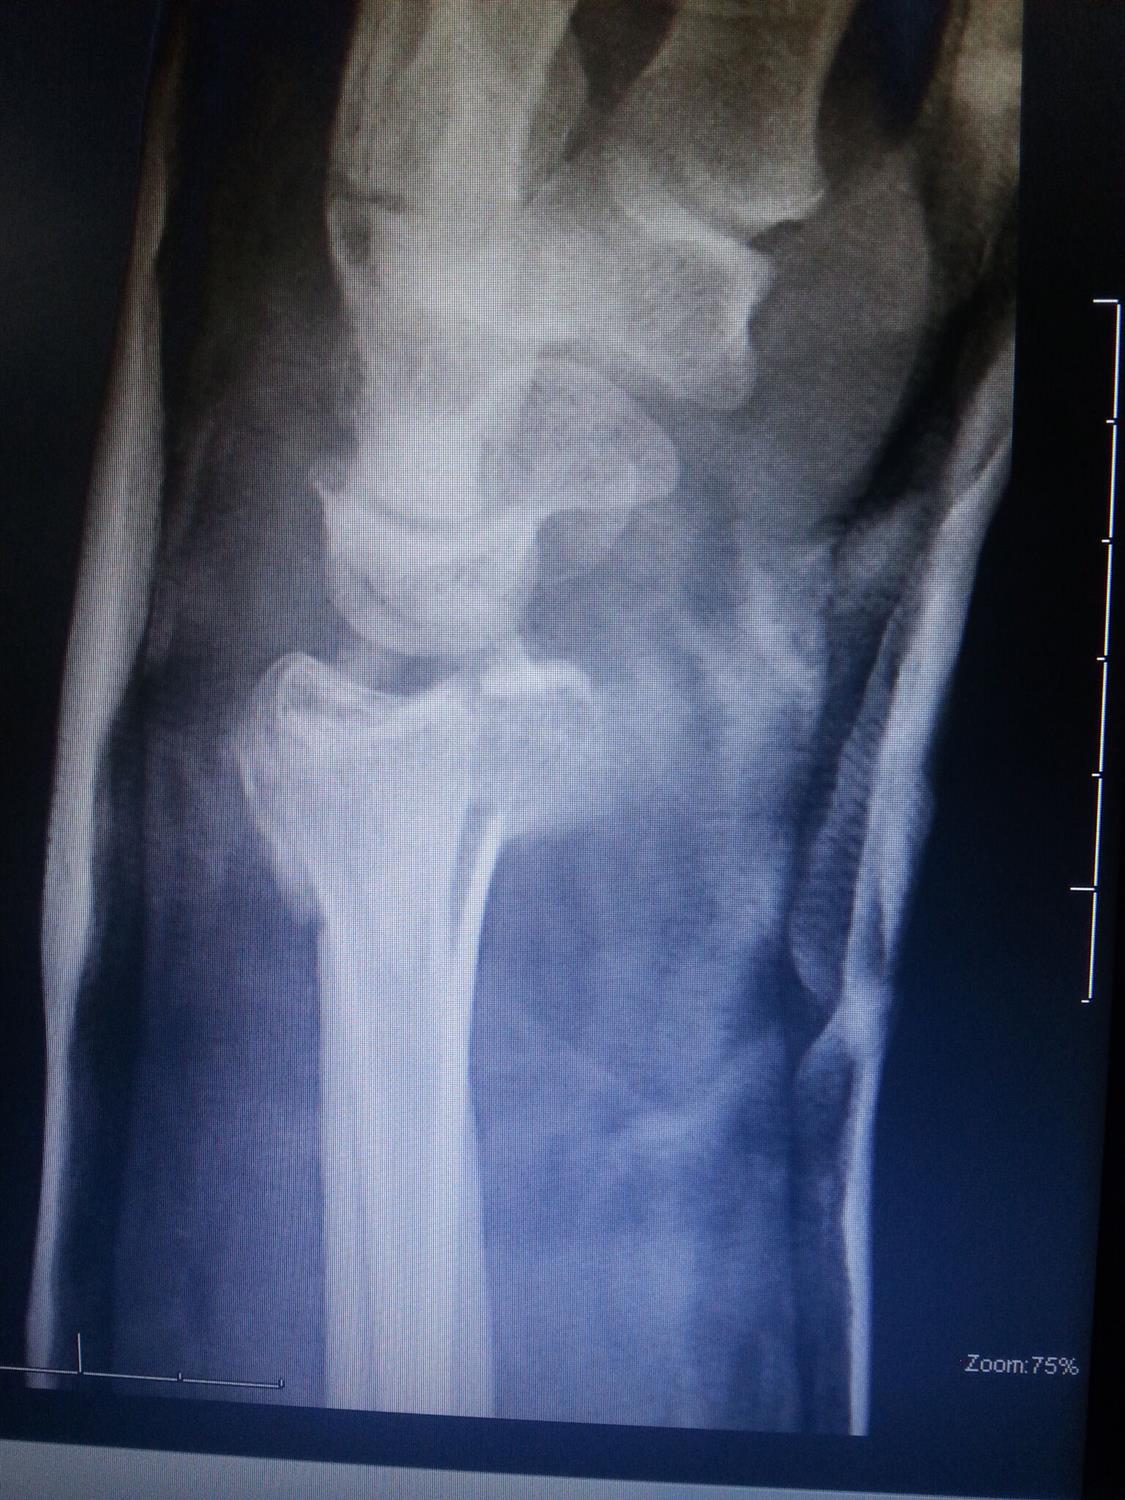

Distal Radius Ulna Fracture Orthobullets . Radial head fracture with an interosseous membrane injury extending to druj unstable relationship between ulna and radius leads to proximal migration of the radius Distal radius fractures are the most common site of pediatric forearm fractures and generally occur as a result of a fall on an outstretched hand with the wrist extended. Ulnar styloid fracture occurs together with distal radius fracture that has high degree of initial displacement associated with. Distal radius fractures are the most common orthopaedic injury and generally result from fall on an outstretched hand. The american academy of orthopaedic surgeons and the american society for surgery of the hand released updated clinical practice guidelines in. Distal radius fracture is usually associated with ulnar styloid fracture. Whether to fix the ulnar styloid or not remains a surgical dilemma as. Radius and ulnar shaft fractures, also known as adult both bone forearm fractures, are common fractures of the forearm caused by.

Radius and ulnar shaft fractures, also known as adult both bone forearm fractures, are common fractures of the forearm caused by. Whether to fix the ulnar styloid or not remains a surgical dilemma as. Distal radius fracture is usually associated with ulnar styloid fracture. Radial head fracture with an interosseous membrane injury extending to druj unstable relationship between ulna and radius leads to proximal migration of the radius Ulnar styloid fracture occurs together with distal radius fracture that has high degree of initial displacement associated with. Distal radius fractures are the most common site of pediatric forearm fractures and generally occur as a result of a fall on an outstretched hand with the wrist extended. Distal radius fractures are the most common orthopaedic injury and generally result from fall on an outstretched hand. The american academy of orthopaedic surgeons and the american society for surgery of the hand released updated clinical practice guidelines in.

Distal Radius Ulna Fracture Orthobullets Ulnar styloid fracture occurs together with distal radius fracture that has high degree of initial displacement associated with. Radius and ulnar shaft fractures, also known as adult both bone forearm fractures, are common fractures of the forearm caused by. Distal radius fractures are the most common site of pediatric forearm fractures and generally occur as a result of a fall on an outstretched hand with the wrist extended. Distal radius fractures are the most common orthopaedic injury and generally result from fall on an outstretched hand. Ulnar styloid fracture occurs together with distal radius fracture that has high degree of initial displacement associated with. The american academy of orthopaedic surgeons and the american society for surgery of the hand released updated clinical practice guidelines in. Distal radius fracture is usually associated with ulnar styloid fracture. Radial head fracture with an interosseous membrane injury extending to druj unstable relationship between ulna and radius leads to proximal migration of the radius Whether to fix the ulnar styloid or not remains a surgical dilemma as.